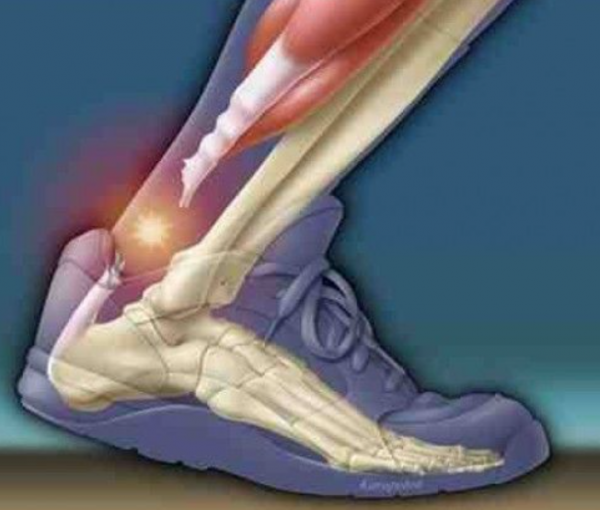

Achilles Tendon Injuries